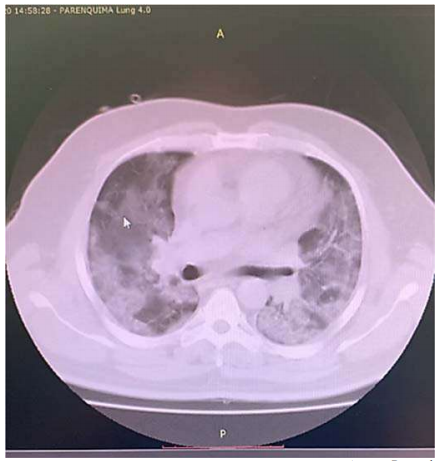

Um paciente de 68 anos de idade, com RT PCR para Sars-CoV-2 reagente (VR = não reagente), evolui com astenia, inapetência, tosse seca e coriza nasal. Realiza exames de imagem, no quinto dia de doença, em tomógrafo de alta definição, em que foram descritas lesões em vidro fosco bilaterais, correspondendo a 25% dos pulmões, podendo estarem associadas a processo inflamatório/infeccioso viral. Segue em acompanhamento domiciliar da doença. No 12º dia de doença, o paciente retorna com rouquidão, cianose de extremidades, apresentando febre de 38 o C e desconforto respiratório com uso de musculatura acessória. Verificam-se ausculta pulmonar com tórax silente, SatO2 = 78% com 15 litros / minuto de oxigênio em máscara facial com reservatório, PA = 87 mmHg x 43 mmHg, FC = 123 bpm e FR = 52 irpm. Os exames indicaram os seguintes resultados: leucograma = 5.400, sem desvios; PCR (proteína C reativa) = 356 (VR = abaixo de 6); ferritina = 11.458 ng/mL (VR = 20 ng/mL a 330 ng/mL); dímero -D = 26 mcg/mL (VR = 0,5 mcg/mL); gasometria pH = 7,109 (VR = 7,35 a 7,45); PaO2 = 53,8 mmHg (VR = 80 mmHg a 100 mmHg); PaCO2 = 104,6 mmHg (VR = 35 mmHg – 45 mmHg); HCO3 = 21 mmol/L (VR = 21 mmol/L a 28 mmol/L); SaO2 = 76,7 % (VR = 95% a 99%). Foi realizada nova tomografia do paciente, cuja imagem parcial pode ser observada a seguir.

Acervo Pessoal

Com base nesse caso clínico, na imagem da tomografia apresentada e nos conhecimentos médicos correlatos, julgue os itens a seguir.

De acordo com as manifestações clínicas, laboratoriais e radiológicas, esse paciente está no estágio III da doença, grave e com hiperinflamação, o que ocorre na minoria dos pacientes acometidos.